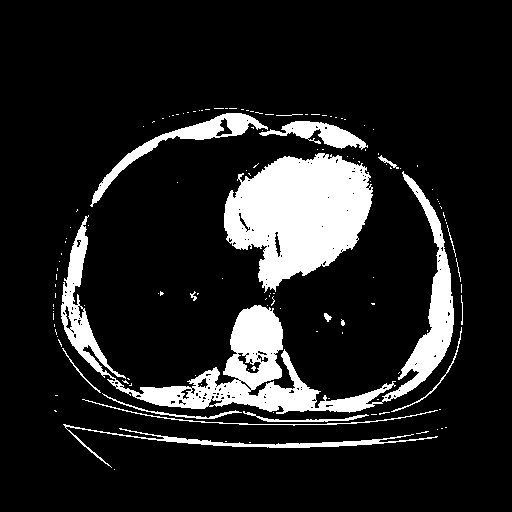

Image Grid

4Γ—3 grid: Rows show different image types (Original NATIVE, Reconstructed NATIVE, Original VENOUS, Generated VENOUS), Columns show windowing techniques (No Window, Lung Window, Mediastinum Window)

Original NATIVE CT scan (input)

Full window (WL 1023.5, WW 4095 β†’ Low βˆ’1024, High +3071)

Actual HU range: [-1024.0, 3071.0]